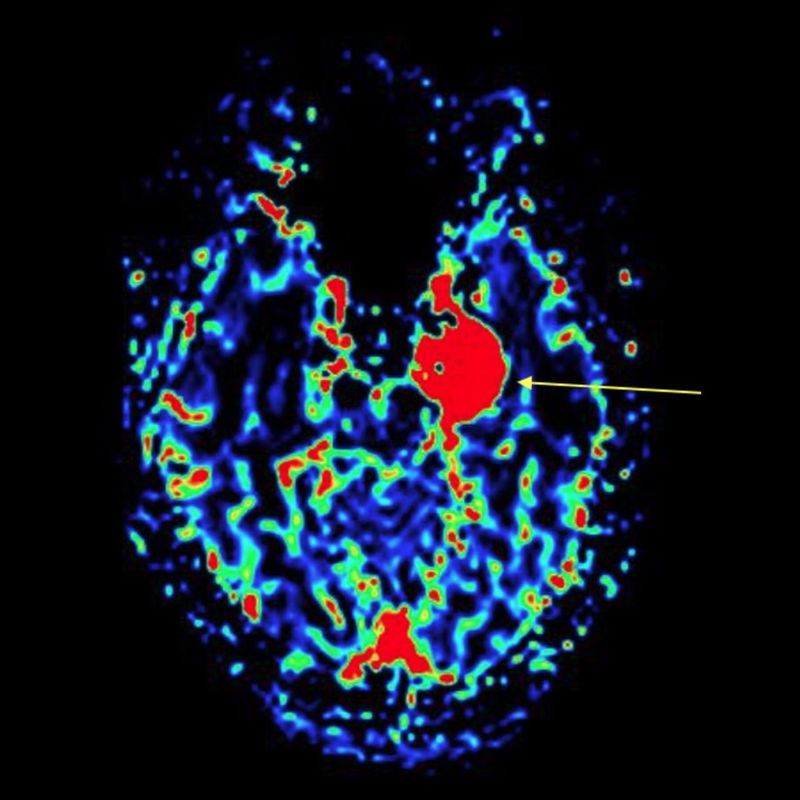

en el curso).A lo largo del curso, se mostrarán los casos clínicos y los respectivos vídeos de las cirugías, que ejemplificarán la aplicación práctica de la anatomía que se está estudiando.